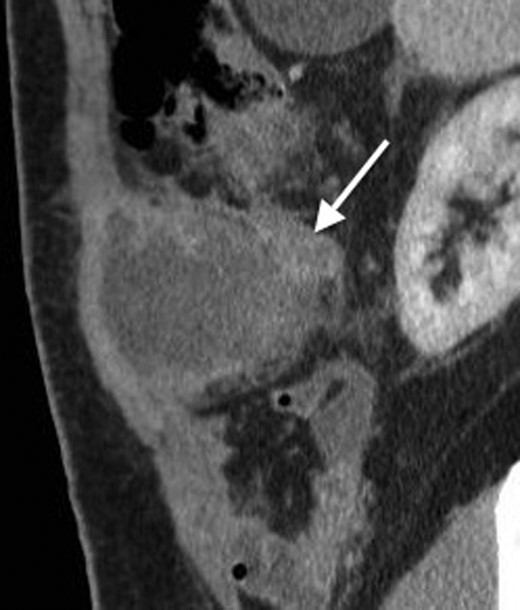

His past surgical history included conservatively managed renal calculi and left inguinoscrotal herniorrhaphy. Right hypochondrial palpation identifying a tender, well-defined, hard, smooth edged, non-pulsatile, non-fluctuant mass (10 × 9 cm). Observations were within normal limits and systemic examinations unremarkable. Haematological results showed the following: albumin 27, WCC 15.7, neutrophils 11.0, CRP 341, amylase 20. Urinalysis, chest and abdominal radiographs (AXR) were normal. Initial resuscitative management was commenced and a contrast enhanced computed tomography (CT) performed. This demonstrated an anterior abdominal wall collection (7 cm) arising from an RUQ appendiceal abscess secondary to acute appendicitis (Figs 1 and 2). Consequent ultrasound (US) guided drainage and pigtail catheter insertion removed 50 ml of frank pus, which isolated pathogens sensitive to penicillin and erythromycin. Following 3 days of intravenous piperacillin and tazobactam (Tazocin®) he was discharged with oral erythromycin. An out-patient barium follow-through and colonoscopy were unremarkable.

A coronal CT with contrast showing the tail of the appendix communicating with the appendiceal abscess.